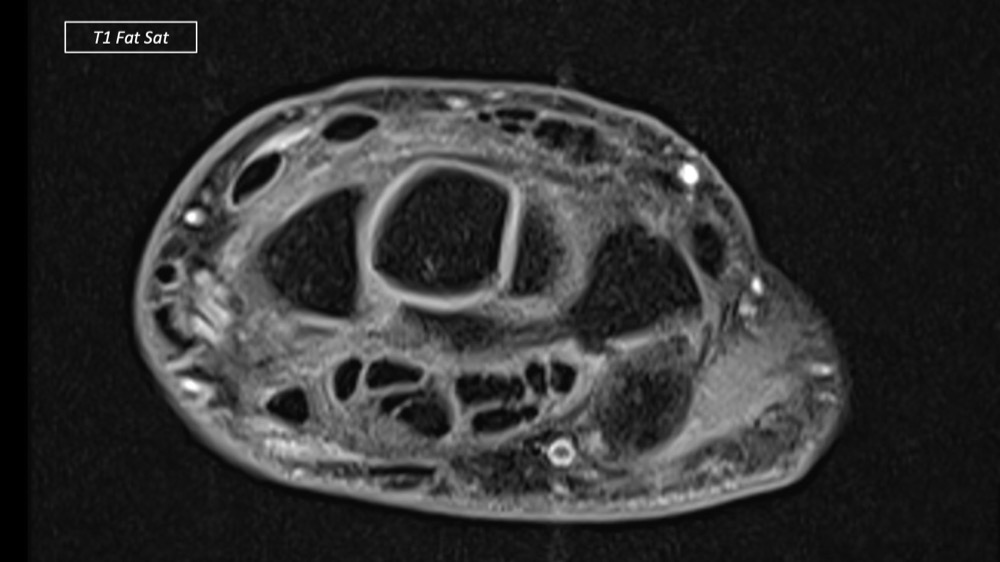

Dupuis / Benoist / Leclerc / Bousson 18/05/2022